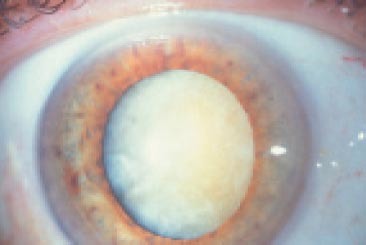

Cataracte brune